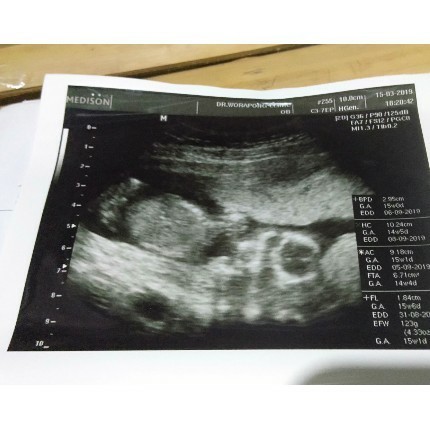

ไปซาวด์มาตอน3เดือนครึ่ง หมอบอกผู้ชาย ตอนนี้เพศชัดแล้วเหรอคับ

3เดือนครึ่ง อวัยวะสร้างหมดแล้วค่ะ ถ้าผู้ชายจะเห็นชัดกว่าผู้หญิง เพราะ ปิกาจู้ มันจะแหลมออกมา หมอเขาดูมานับไม่ถ้วนเค้าดูออกค่ะ ส่วนตัวเรานั้นถ้าหมอไม่บอกว่าตรงไหนคืออะไร คือมองไม่ออกเลย 5555

ตอนนี้13 3วัน ไปซาวด์ดูความสมบูรณ์ของร่างกายค่ะ แต่หมอก็ทักมาว่าผู้ชาย ตกใจเกมือนกันค่ะว่ารุ้เร็วมาก แต่หมอบอกว่ายังไม่ชัดเจนเท่าไหร่ค่ะ

ยินดีด้วยค่ะ ผช เห็นชัดมากค่ะว่าเป็นผช พ่อลองดูของลูกบ้านนี้สิคะมีว่าอะไรคล้ายๆกัน ตอนที่ซาวด์เพศบ้านนี้20 w ค่ะ

14w น้องหันหน้ามาโชว์ทุกสิ่งอย่าง หมอบอกน่าจะเป็นผู้ชายเหมือนกันค่ะ